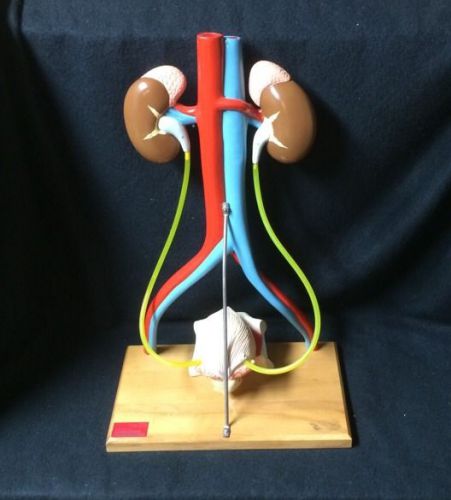

Denoyer Geppert - A55 Free Standing Urinary System w/ Kidneys Anatomical Model